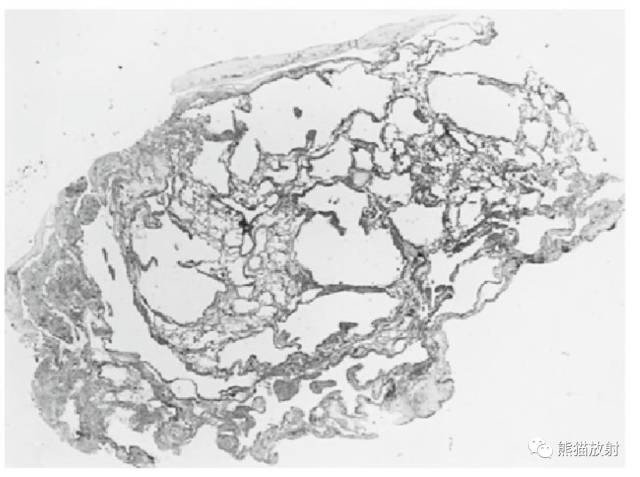

本病的标志是肺实质的囊状破坏。

在HRCT上,LAM病例的特征性表现为无数薄壁肺囊肿,周围绕以较正常的肺实质。这些囊肿的直径范围常为2mm~5cm,也可以更大。囊肿的大小倾向于随病变进展而增大。发生在TSC中的LAM与单发LAM表现相同。

在大多数病例中,HRCT上囊肿之间的肺实质正常。